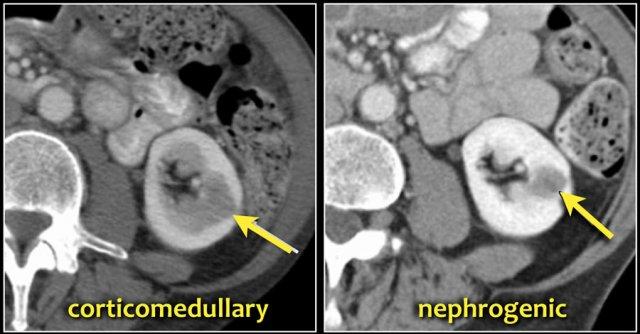

Cột Bertin nổi bật, sự phồng lồi bờ viền thận và phì đại thận khu trú có thể trông giống như một khối thận trên siêu âm, hình ảnh không tiêm thuốc cản quang và CT ở thì thận (nephrogenic phase).

Ở thì vỏ-tủy (corticomedullary phase), cấu trúc vỏ-tủy bình thường trong các giả u này có thể được nhận diện rõ ràng, giúp phân biệt chúng với các tổn thương thực sự.

Giả u (Pseudotumor). Thì thận (Nephrogenic phase) ở bên trái và thì vỏ-tủy (Corticomedullary phase) ở bên phải.

Đây là một trường hợp khác.

Ở thì thận, có thể đặt ra nghi vấn về sự hiện diện của một tổn thương ở thận trái.

Tuy nhiên, ở thì vỏ-tủy, rõ ràng đây là một giả u (pseudotumor).